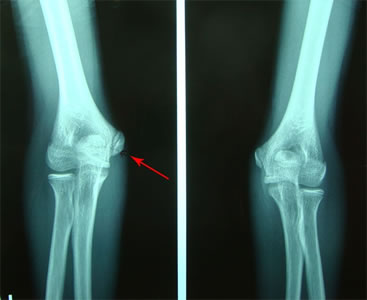

今回の患者様にも専門整形外科での検査などを依頼し、実施して頂きました。以下の写真(↓)は、左右の肘関節レントゲン画像です。矢印の先が剥離骨折部です。

患側の右肘拡大です。

赤色矢印の先に、横向きに黒い線が確認できますでしょうか。

次に健側の左肘拡大です。

緑矢印の先には、患側と異なり、横方向の黒い線がありません。